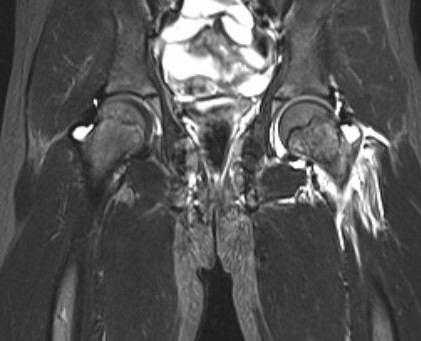

Septic arthritisSeptic arthritis

Advanced AVN and collapse after hip septic arthritis

Paed Hip OMPaed OM